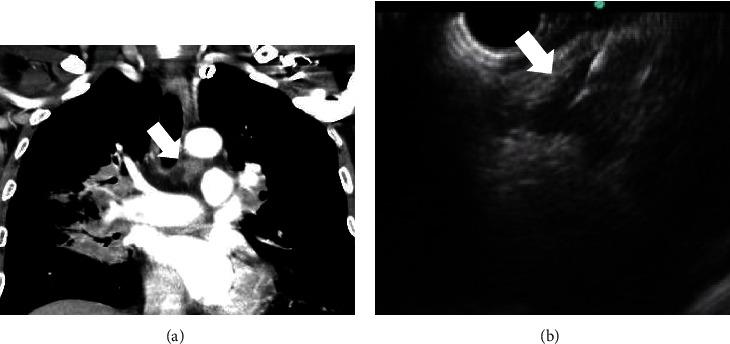

From May 2006 to January 2017, patients with mediastinal lymphadenopathy, who received an EUS-guided trucut biopsy or an FNA biopsy, were retrospectively reviewed. Demographic data, endosonographic characteristics of LNs including size, shape, border, echotexture, and echogenicity, diagnostic yield, and adverse events between the trucut needle group and aspiration needle group were compared.

A total of 69 patients (trucut group, = 33 vs. aspiration group, = 36) were identified. There were no significant differences in demographic data, indication for an EUS-guided biopsy, location of LNs, number of needle passes, and endosonographic features of LNs between the two groups. The sizes of LNs were larger in the trucut group than in the aspiration group (28.9 ± 14.0 mm vs. 21.1 ± 8.8 mm, = 0.007). However, there was no significant difference in the ratio of LNs that were ≥10 mm in both groups. The overall accuracy of the EUS-guided biopsy for the diagnosis of malignant lesions was 79.7% (55/69). There were no significant differences in the histological diagnostic yield of malignant LNs between the two groups. There were no significant procedure-related adverse events in both groups.

The EUS-guided biopsy can be a useful method for histologic evaluation of mediastinal nodal lesions.